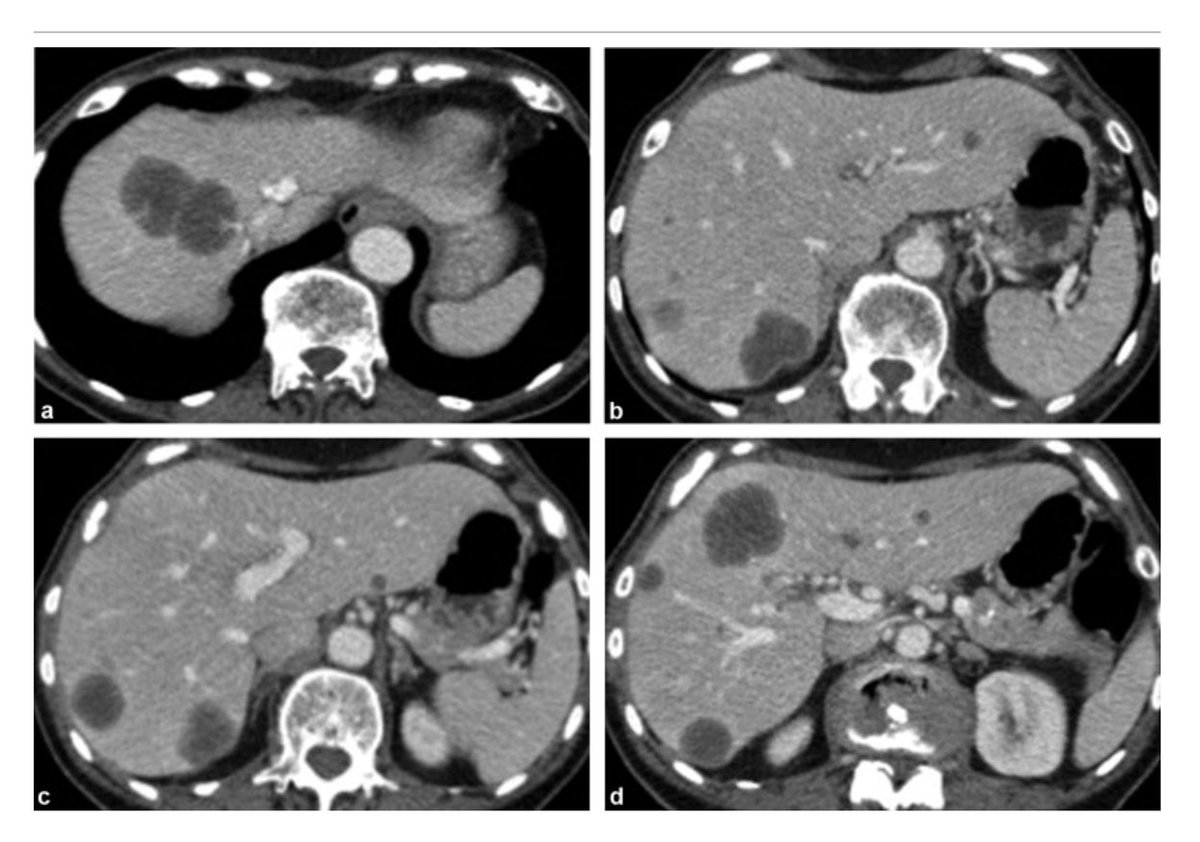

🩻CTAP: multiple liver, peritoneal mets